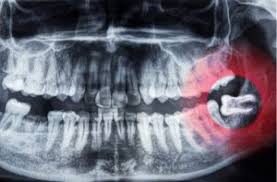

Many dentists believe it's better to remove wisdom teeth at a younger age, before the roots and bone are fully formed, and when recovery is generally faster after surgery. Our powerful toothpaste collection helps reverse early gum damage. What to do after wisdom tooth extraction? Find out during your appointment. If you've started to develop your wisdom teeth (this usually occurs around ages 17 to 25), you might have experienced pain while chewing, swelling in the back of your mouth or jaw, or limited jaw movements. If wisdom teeth don't have enough room to come in properly, they may crowd or damage nearby teeth. Oct 27, 2020 · there are many signs that your wisdom teeth need to be removed, but in this article, we covered 13 of them: You can also tell if you need your wisdom teeth removed due to any discomfort they may be causing you.

Crest.com has been visited by 10k+ users in the past month Reverses early gum damage · reverses gingivitis Crest.com has been visited by 10k+ users in the past month Could a new smile make you more confident? Stiffness or pain in your jaw; If you've started to develop your wisdom teeth (this usually occurs around ages 17 to 25), you might have experienced pain while chewing, swelling in the back of your mouth or jaw, or limited jaw movements. Oct 27, 2020 · there are many signs that your wisdom teeth need to be removed, but in this article, we covered 13 of them: You can also tell if you need your wisdom teeth removed due to any discomfort they may be causing you. Do wisdom teeth holes close? What happens after wisdom tooth extraction? Find out during your appointment. Many dentists believe it's better to remove wisdom teeth at a younger age, before the roots and bone are fully formed, and when recovery is generally faster after surgery. Our powerful toothpaste collection helps reverse early gum damage.

When wisdom teeth emerge, they can cause complications like tooth decay, pain, and infection. Crest.com has been visited by 10k+ users in the past month Gum detoxify deep clean, detoxify gentle whitening Some people have enough space in their jaw to let wisdom teeth come in and are able to clean them. Crest.com has been visited by 10k+ users in the past month Reverses early gum damage · reverses gingivitis Find out during your appointment. Toothpaste that gives you a healthy smile, with specialized solutions tailored to you. Pain in the back of your mouth; Maybe your mouth is too small to make room for them, or the teeth could be growing at an. Feb 15, 2021 · wisdom teeth do not necessarily have to be removed. As your wisdom teeth grow in, you may experience aches and pains at the back of your mouth. Gum detoxify deep clean, detoxify gentle whitening

The teeth could be stuck, or impacted. Jul 01, 2021 · here are 7 signs you may need your wisdom teeth removed: Could a new smile make you more confident? When wisdom teeth emerge, they can cause complications like tooth decay, pain, and infection. That means they can't break through your jaw and into your mouth. Maybe your mouth is too small to make room for them, or the teeth could be growing at an. If wisdom teeth don't have enough room to come in properly, they may crowd or damage nearby teeth. Gum detoxify deep clean, detoxify gentle whitening Some people have enough space in their jaw to let wisdom teeth come in and are able to clean them. Find out during your appointment. Crest.com has been visited by 10k+ users in the past month Find out during your appointment. Gum detoxify deep clean, detoxify gentle whitening